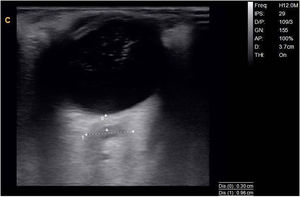

Se realizó con ecógrafo portátil (Chison Q9 con sonda lineal de 7MHz) una ecografía orbitaria en modo B, donde se obtienen un diámetro del nervio óptico en el lado derecho de 9,6mm (fig. 1) y en el lado izquierdo de 6,4mm.

La medición del diámetro del nervio óptico se ha observado que tiene una buena correlación como signo indirecto no invasivo para detectar una hipertensión endocraneal; los estudios se han realizado principalmente en casos con hipertensión endocraneal idiopática, comprobados posteriormente mediante punción lumbar1. Esta técnica es fácil de realizar con un mínimo entrenamiento en neurosonografía y conocimiento teórico. Precisa de un ecógrafo con modo B, con una sonda lineal multifrecuencias de 3-9MHz. Se explora la órbita mediante ventana transorbitaria. El paciente se coloca en posición supina, con la cabeza elevada unos 20-30°. Con los ojos cerrados se coloca gel sobre el párpado superior. La sonda se dispone en posición axial y se visualiza la zona de la papila y la región retrobulbar del nervio óptico; desde esta localización se miden unos 3mm en profundidad siguiendo el trayecto del nervio óptico, en esa zona se calcula el diámetro entre los bordes externos del área hiperecogénica del nervio óptico (corresponde a la vaina del nervio óptico) (fig. 1). Los estudios evaluados muestran una adecuada diferencia interobservador y los criterios de normalidad se establecen en 5,4±0,6mm1–3.